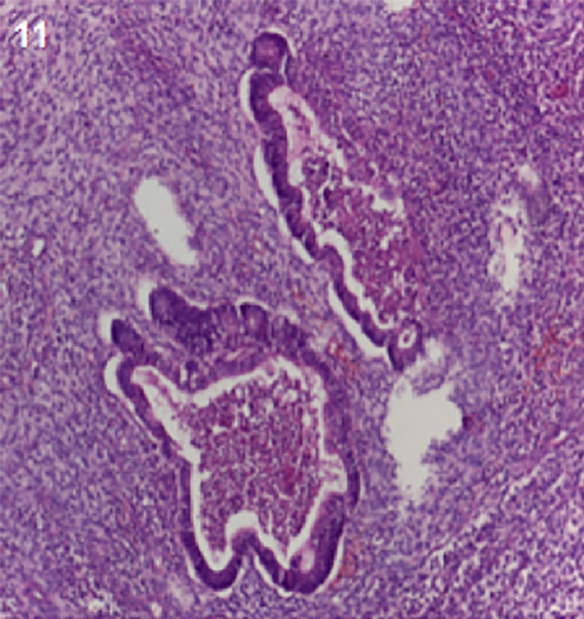

A los 3 meses el paciente reingresa debido a estado confusional. Se realiza nueva RM mostrándose recidiva tumoral en resonancia magnética (Figuras 9 y 10). El paciente fallece aproximadamente 5 meses luego del procedimiento quirúrgico debido a progresión tumoral.

Figura 9 y 10. Resonancia 3 meses